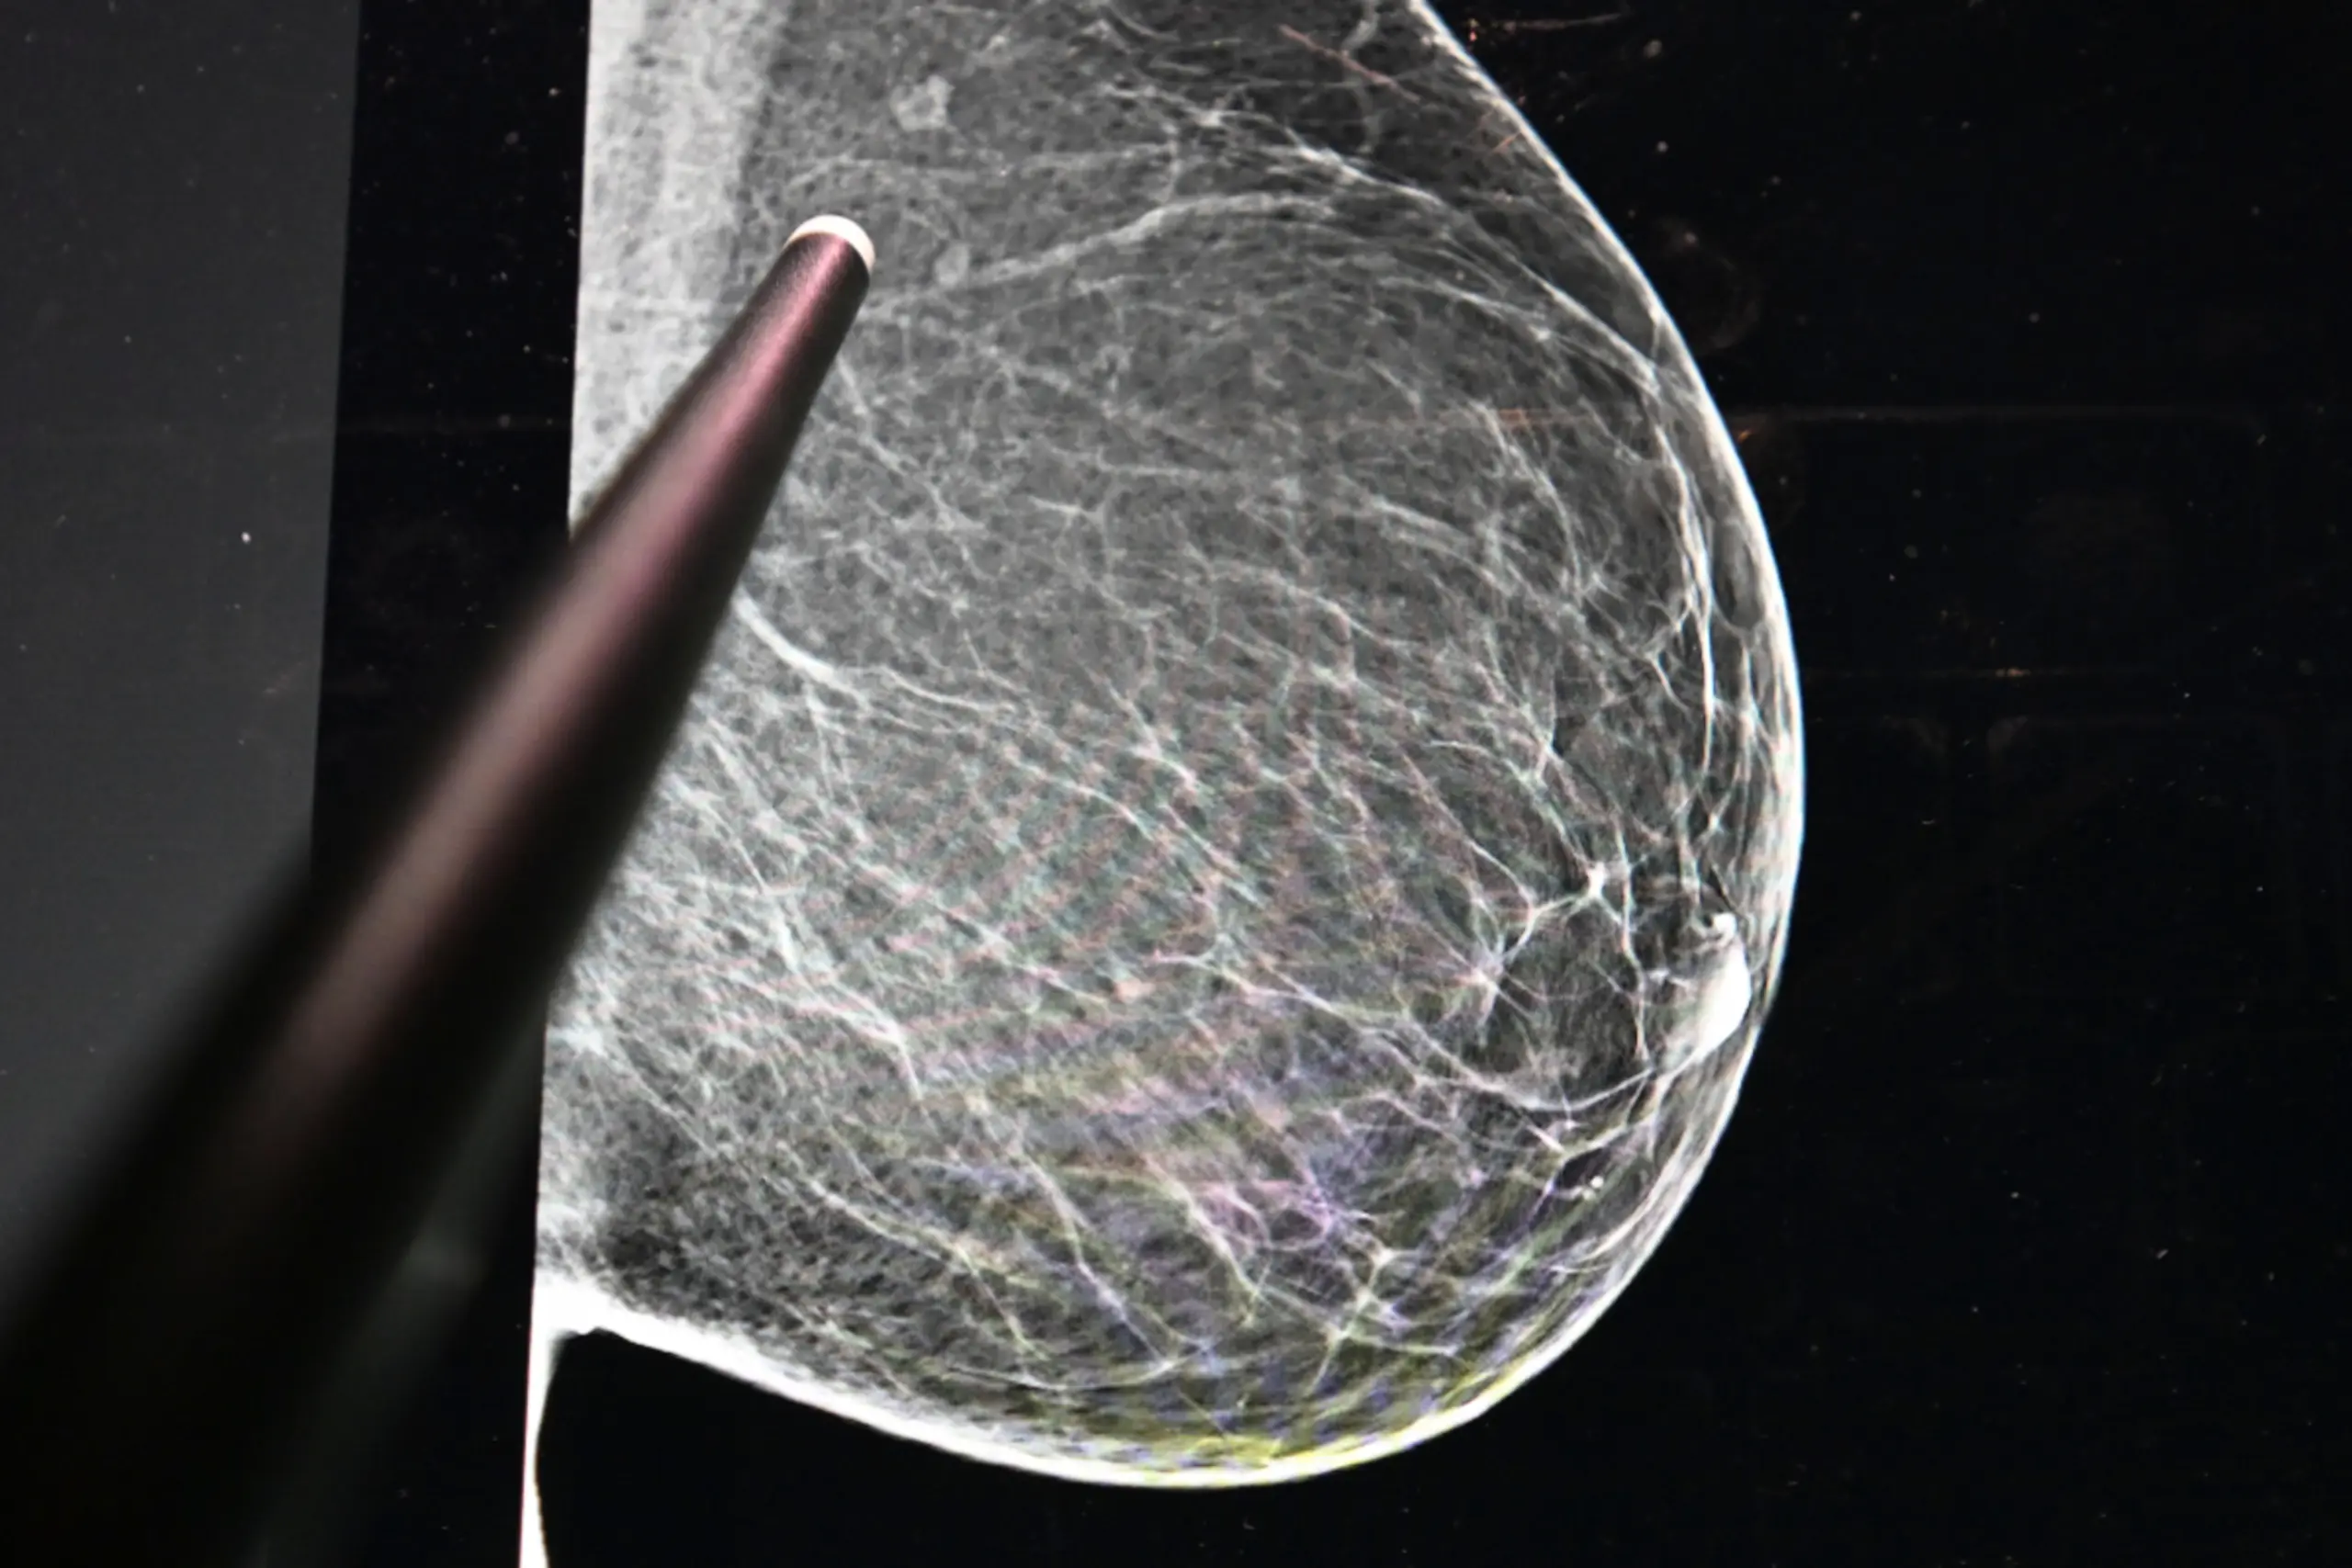

++ THEMENBILD ++ Illustration zum Thema "Mammografie / Brustkrebsvorsorge / Brustkrebs-Früherkennung / Radiologie / Röntgen / Frauen /Gesundheit" - Ein digitales Bruströntgenbild, aufgenommen am Mittwoch, 19. November 2025.